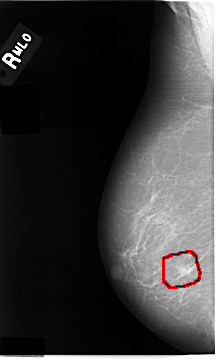

C_0014_1.RIGHT_MLO

RIGHT_MLO LINES 4664 PIXELS_PER_LINE 2800 BITS_PER_PIXEL 12 RESOLUTION 50 OVERLAY

FILE: C_0014_1.RIGHT_MLO.OVERLAY

TOTAL_ABNORMALITIES 1

ABNORMALITY 1

LESION_TYPE MASS SHAPE IRREGULAR MARGINS MICROLOBULATED

ASSESSMENT 5

SUBTLETY 4

PATHOLOGY MALIGNANT

TOTAL_OUTLINES 1

BOUNDARY